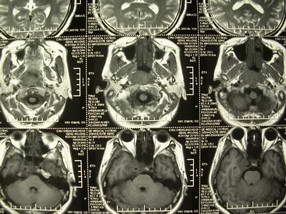

扫描示鼻咽腔不对称,中度狭窄,右侧咽隐窝消失,局部软组织肿块,鼻咽右侧壁增厚形成肿块,突入鼻咽腔,肿块平扫呈等密度,肿块向深部侵润,右侧翼内外肌受侵,右侧咽旁间隙变窄;向后生长,头长肌界线欠清,向后上生长侵犯同侧颈动脉鞘区。双侧海绵窦增宽,内见软组织影与鼻咽部肿块相连。考虑鼻咽癌。鼻咽癌主要是放射治疗,且效果较好;到当地有治疗设备较大医院治疗即可。

典型鼻咽癌侵犯右侧海绵窦(对放疗敏感)

还是先确诊,如果是鼻咽癌,一般行放射治疗;这例患者我首先考虑鼻咽癌